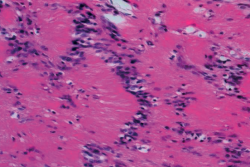

Para confirmar el diagnóstico, se realizaron una electromiografía del miembro inferior derecho, con resultados dentro de la normalidad, y una resonancia magnética (RM) de tobillo como podemos ver en la Figura 2.

Figura 2. Resonancia magnética (RM) del tobillo derecho. A: imagen de masa en el plano coronal del tobillo potenciada en T2 con clásico aumento de señal de la lesión neurógena, donde se muestra lesión con su rama aferente y eferente dependiente del nervio tibial posterior; B: imagen sagital potenciada en T2. La flecha indica un aumento de la intensidad de la señal de manera heterogénea en la periferia de la masa de tejido blando y una disminución de la intensidad de la señal en el centro de la masa (signo de la diana); C: imagen de corte transversal de RM ponderada en T1 que muestra una masa homogénea de baja intensidad retromaleolar.

El radiólogo informó esta como lesión nodular hiperintensa homogénea en T2 e isointensa en T1 de 19 × 15 × 14 mm de tamaño al nivel del tercio medio de la grasa de Kager y posterior y medial al músculo flexor largo del hallux. Presenta continuidad con una estructura tubular en su polo superior e inferior muy posiblemente nerviosa y compatible con el diagnóstico de tumor neuronal de la vaina nerviosa del NTP. También se aprecia un discreto derrame en la articulación del tobillo y un proceso de Steida moderadamente prominente.

Reconocemos que la RM es el patrón oro para identificar estos tumores dentro del NTP y diferenciar entre schwannoma, neurofibroma y otros tumores de los tejidos blandos. Un schwannoma se origina y crece en la periferia del nervio, provocando compresión y desplazamiento lateral o medial del nervio. Por el contrario, los neurofibromas se originan dentro del tejido neural, con fibras nerviosas atrapadas dentro del tumor. El tumor suele aparecer hipointenso en las secuencias potenciadas en T1 e hiperintenso en las secuencias potenciadas en T2, aunque el patrón característico del schwannoma en RM es el llamado signo de la diana, que se observa en las imágenes ponderadas en T2. Varma(25) observa este signo en el 52% de los casos de su trabajo, al igual que nosotros lo hemos identificado en nuestra paciente (Figura 2), y consiste en un borde hiperintenso y un núcleo hipointenso, que corresponden histológicamente al tejido mixomatoso periférico y al tejido fibrocolágeno central, respectivamente.